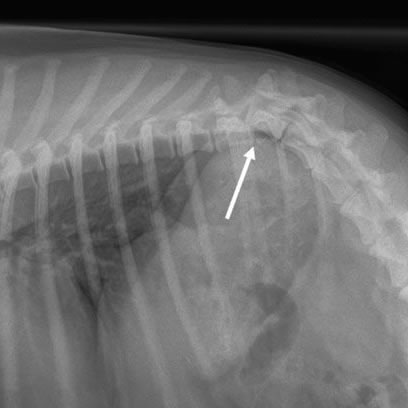

Fraturas em Ossos e Coluna

Fraturas em ossos longos e na coluna vertebral